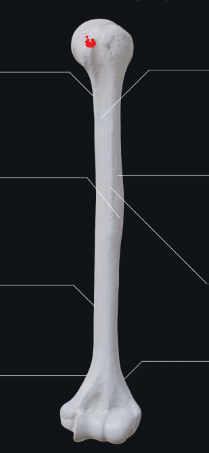

head

lesser tubercle

greater tubercle

surgical neck